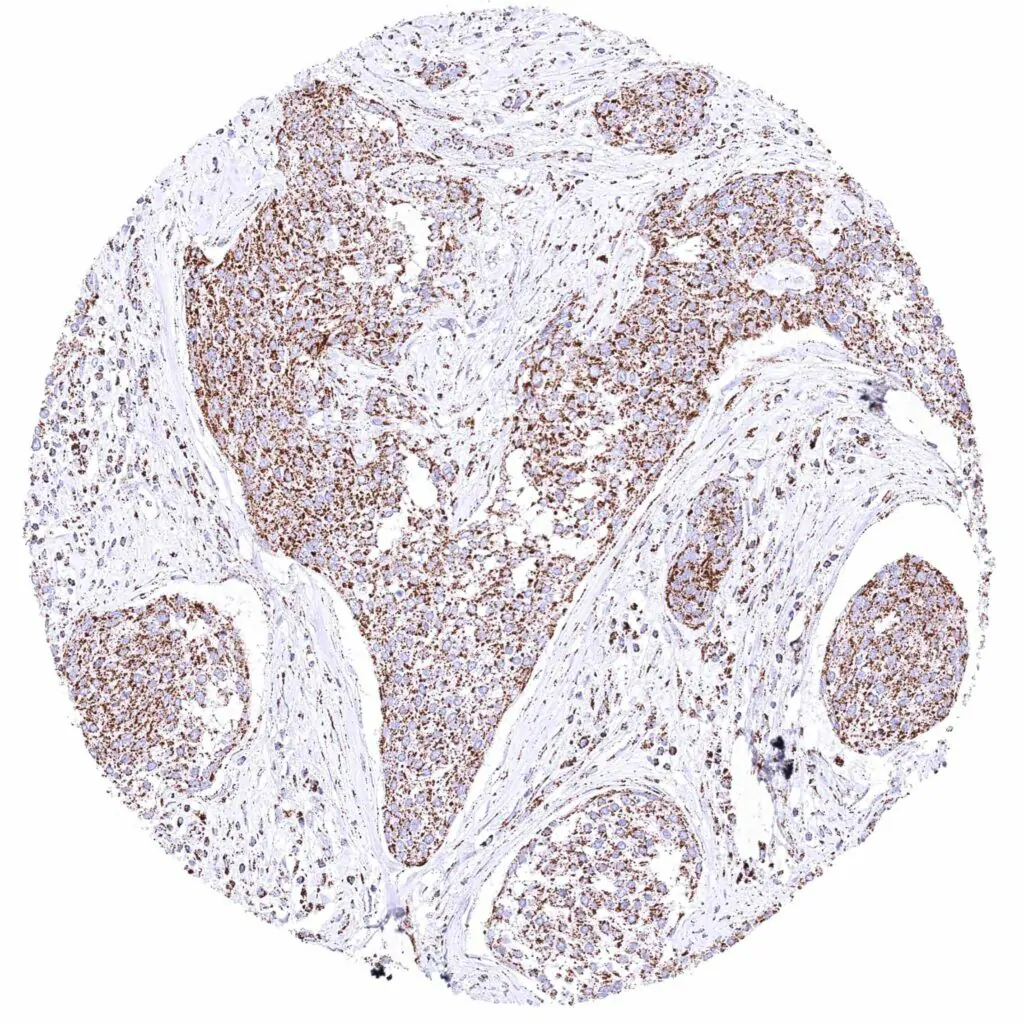

Breast – Invasive lobular breast cancer with strong cytoplasmic ATP5J staining of all tumor cells.